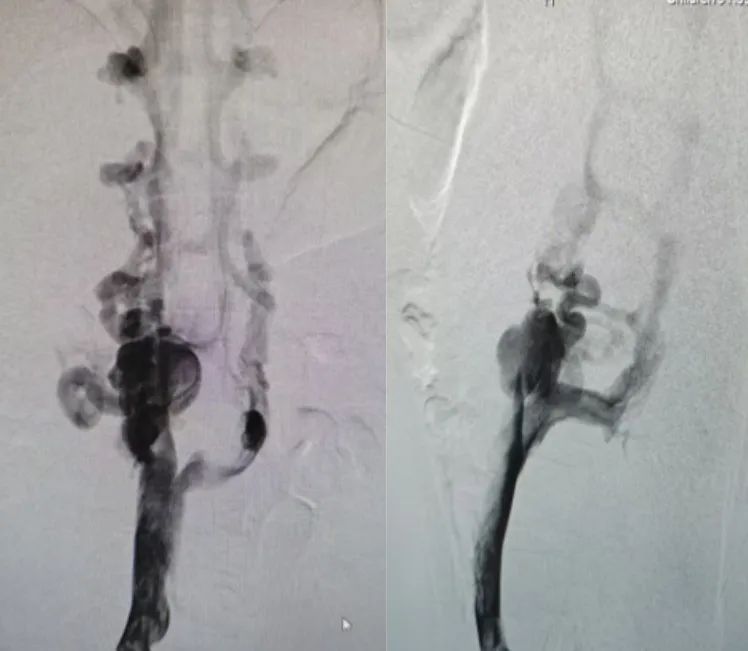

在制定了严谨的治疗方案后,于12月10日,为患儿进行了下腔静脉狭窄球囊扩张术。术中可见下腔静脉肾段至下腔静脉肝段未见下腔静脉显影,双侧可见侧支循环建立,经过血管再通,术后造影提示下腔静脉狭窄段缓解并再通,疾病得以缓解。患儿术后半月,未再出现腹痛,告别了两年来疾病对身体的折磨,这个正值花季的少女终于迎来了自己健康的青春时光。

股静脉入路,下腔静脉正侧位造影,肾段上下腔静脉未显影,双侧腰升静脉异常粗大侧枝循环